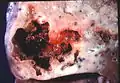

Lung abscess is a type of liquefactive necrosis of the lung tissue and formation of cavities (more than 2 cm)[1] containing necrotic debris or fluid caused by microbial infection.

Lung abscesses are often on one side and single involving posterior segments of the upper lobes and the apical segments of the lower lobes as these areas are gravity dependent when lying down. Presence of air-fluid levels implies rupture into the bronchial tree or rarely growth of gas forming organism.